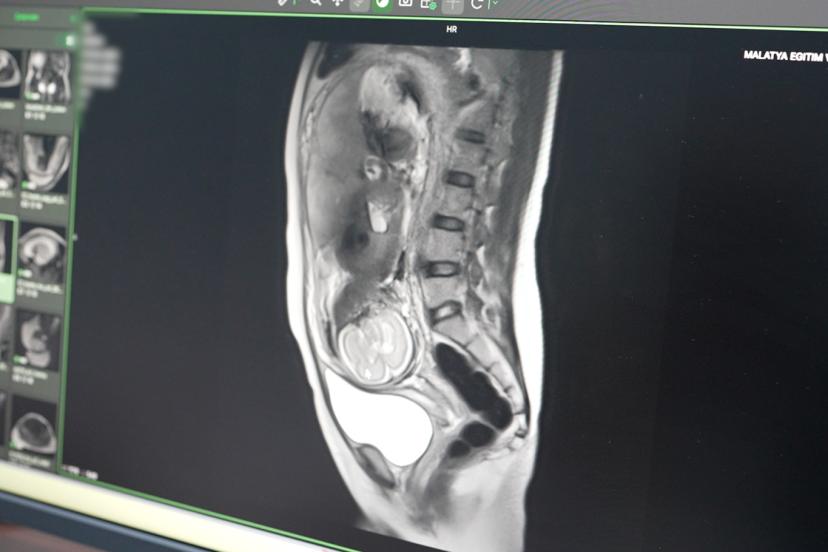

Hastanede uygulanmaya başlayan bir diğer özellikli incelemenin fetal MR olduğunu belirten Petik, anne karnındaki bebeğin gelişim bozuklukları, doğumsal anomaliler ve riskli durumlarının detaylı şekilde değerlendirilebildiğini ifade etti. Fetal MR sayesinde kadın hastalıkları ve doğum uzmanlarının tanı süreçlerinin daha güçlü hale geleceğini vurgulayan Petik, doğum öncesi alınacak tedbirlerin de bu sayede daha doğru planlanabileceğini söyledi.

Açıklamalarında örnek bir vakaya da değinen Petik, 35-40 yaşlarında erkek bir hastanın kalp yetmezliği şikâyetiyle kendilerine yönlendirildiğini belirtti. Yapılan kardiyak MR incelemesinde hastanın sol ventrikül duvar kalınlığının yaklaşık 30 milimetreye ulaştığının tespit edildiğini ifade eden Petik, bu durumun hastanın yaşam kalitesi ve performansını ciddi şekilde etkilediğini söyledi.

Söz konusu hastalığın klasik anjiyografi ile anlaşılmasının mümkün olmadığını belirten Petik, ancak ileri kardiyak görüntüleme yöntemleriyle tanı konulabildiğini vurguladı. Hastaya Yamaguchi Sendromu olarak bilinen özel bir kalp kası hastalığı tanısı konulduğunu söyleyen Petik, erken tanı sayesinde uygun tedavi planlamasının yapıldığını ve ilerleyen dönemde oluşabilecek ciddi kalp yetmezliği riskine karşı önlem alınabildiğini ifade etti.